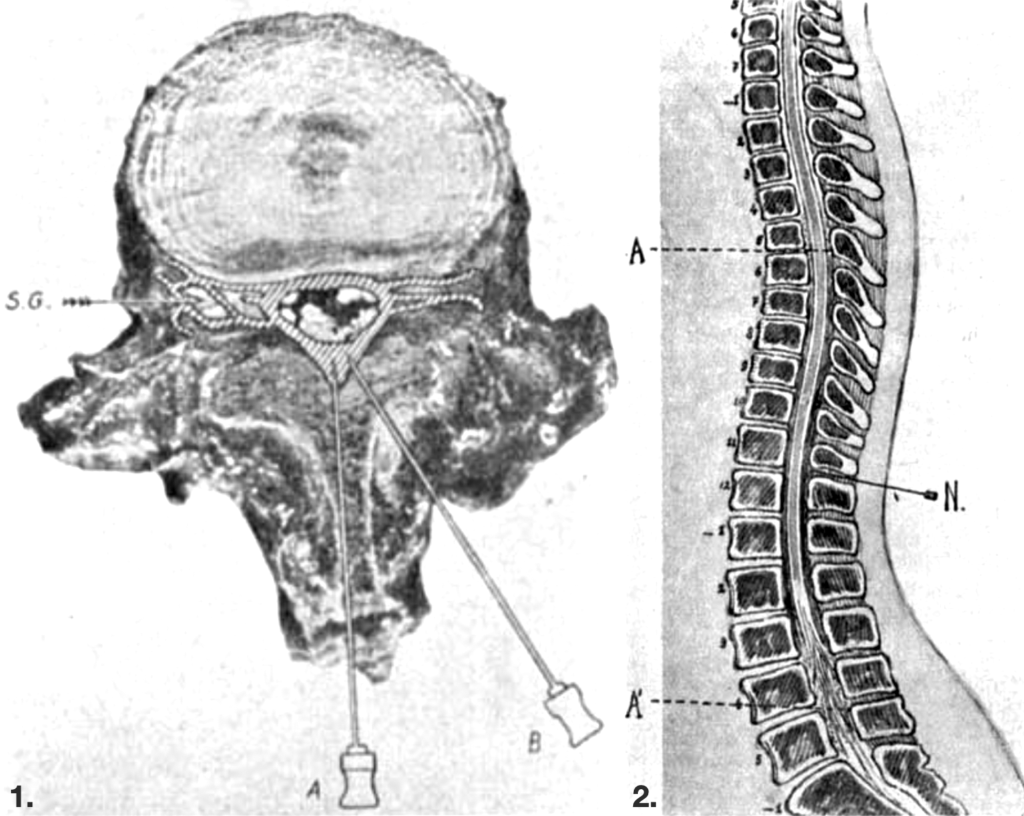

2. Sagittal section of the spinal column showing cranio-caudal diffusion of local anaesthetic within the epidural space, producing controlled segmental blockade without intrathecal injection. [A-A1 = diffusion of anaesthestic; N = needle in epidural space] Dogliotti 1933

Dogliotti described segmental peridural anaesthesia with the injection of local anaesthetic into the epidural space so that it could act on spinal nerves along their course “between the dura mater and the intervertebral canals”. He determined this method would be “an intermediate position between the Corning–Bier method of spinal anesthesia and paravertebral anesthesia”, allowing safe and targeted blockade of selected spinal segments.

Through anatomical dissection, cadaveric injection studies, radiological imaging, and clinical observation, Dogliotti demonstrated that epidural anaesthesia acts primarily on the spinal nerves and ganglia extradurally, with “only a very small quantity” of anaesthetic passing into the cerebrospinal fluid. His contributions assisted in the transition of epidural anaesthesia from experimental innovation to standard clinical practice.